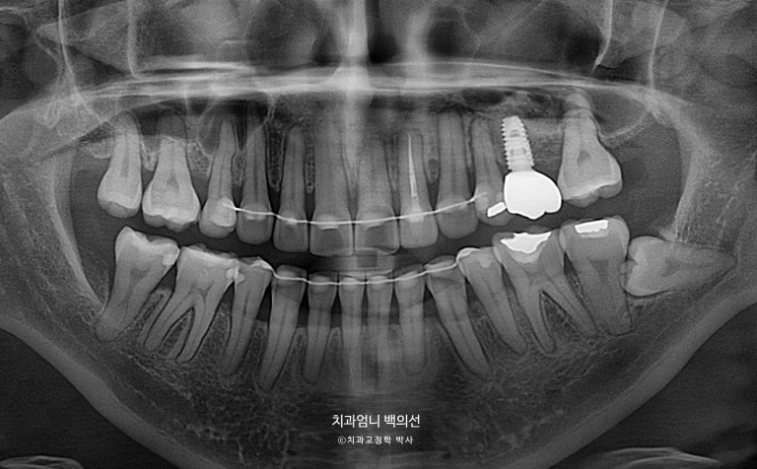

23.08

엑스레이상 좌측 위 첫번째 작은어금니쪽으로 두 번째 작은어금니가 쓰러지며 공간이 없어진 것이 보입니다.

어금니 교합관계는 2급입니다.

치료시작 1년 3개월차, 결손된 큰어금니 공간이 충분히 확보되어 드디어 임플란트를 식립했습니다.

파란 화살표 임플란트가 들어가며 좌우 치아갯수가 맞아졌습니다.

덕분에 중심선도 개선하고 어금니 교합관계도 1급이 되었으며 앞니가 뒤로 쓰러진 옥니도 고칠 수 있었습니다.

1년 8개월에 걸친 재교정 기간동안 추가적인 치근흡수는 없었으며 치근형행도는 처음보다 개선이 되었습니다.